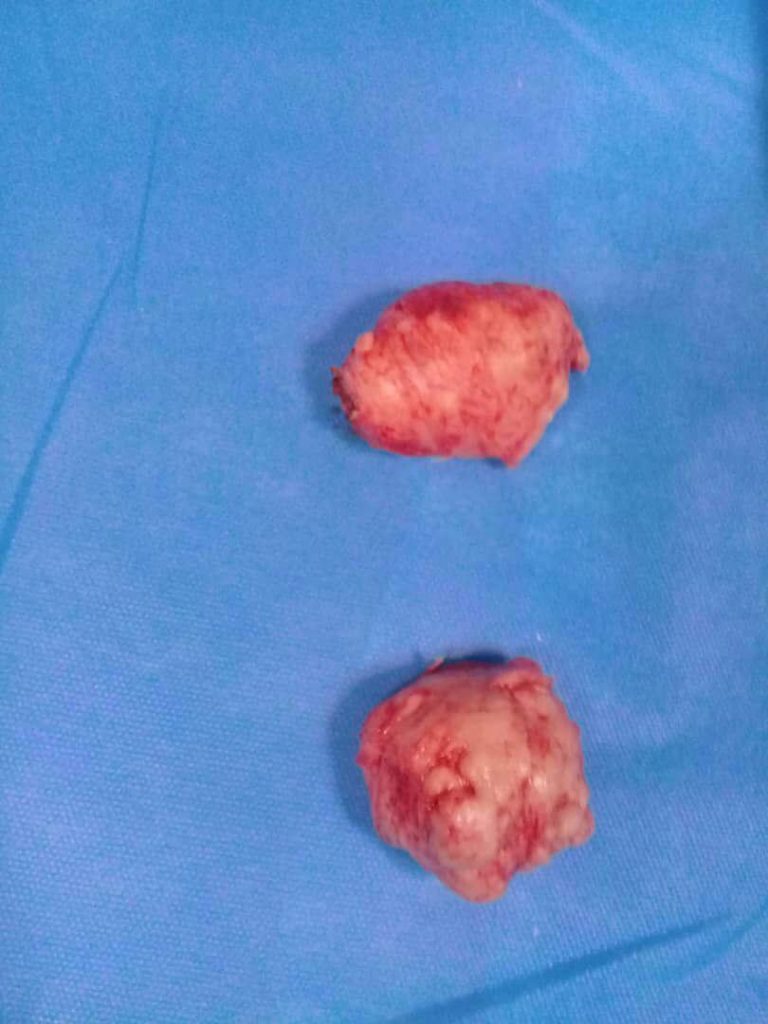

جراحی سنگ به روش بسته و PCNL

- درمان سنگ کلیه

- از بین بردن سنگ کلیه